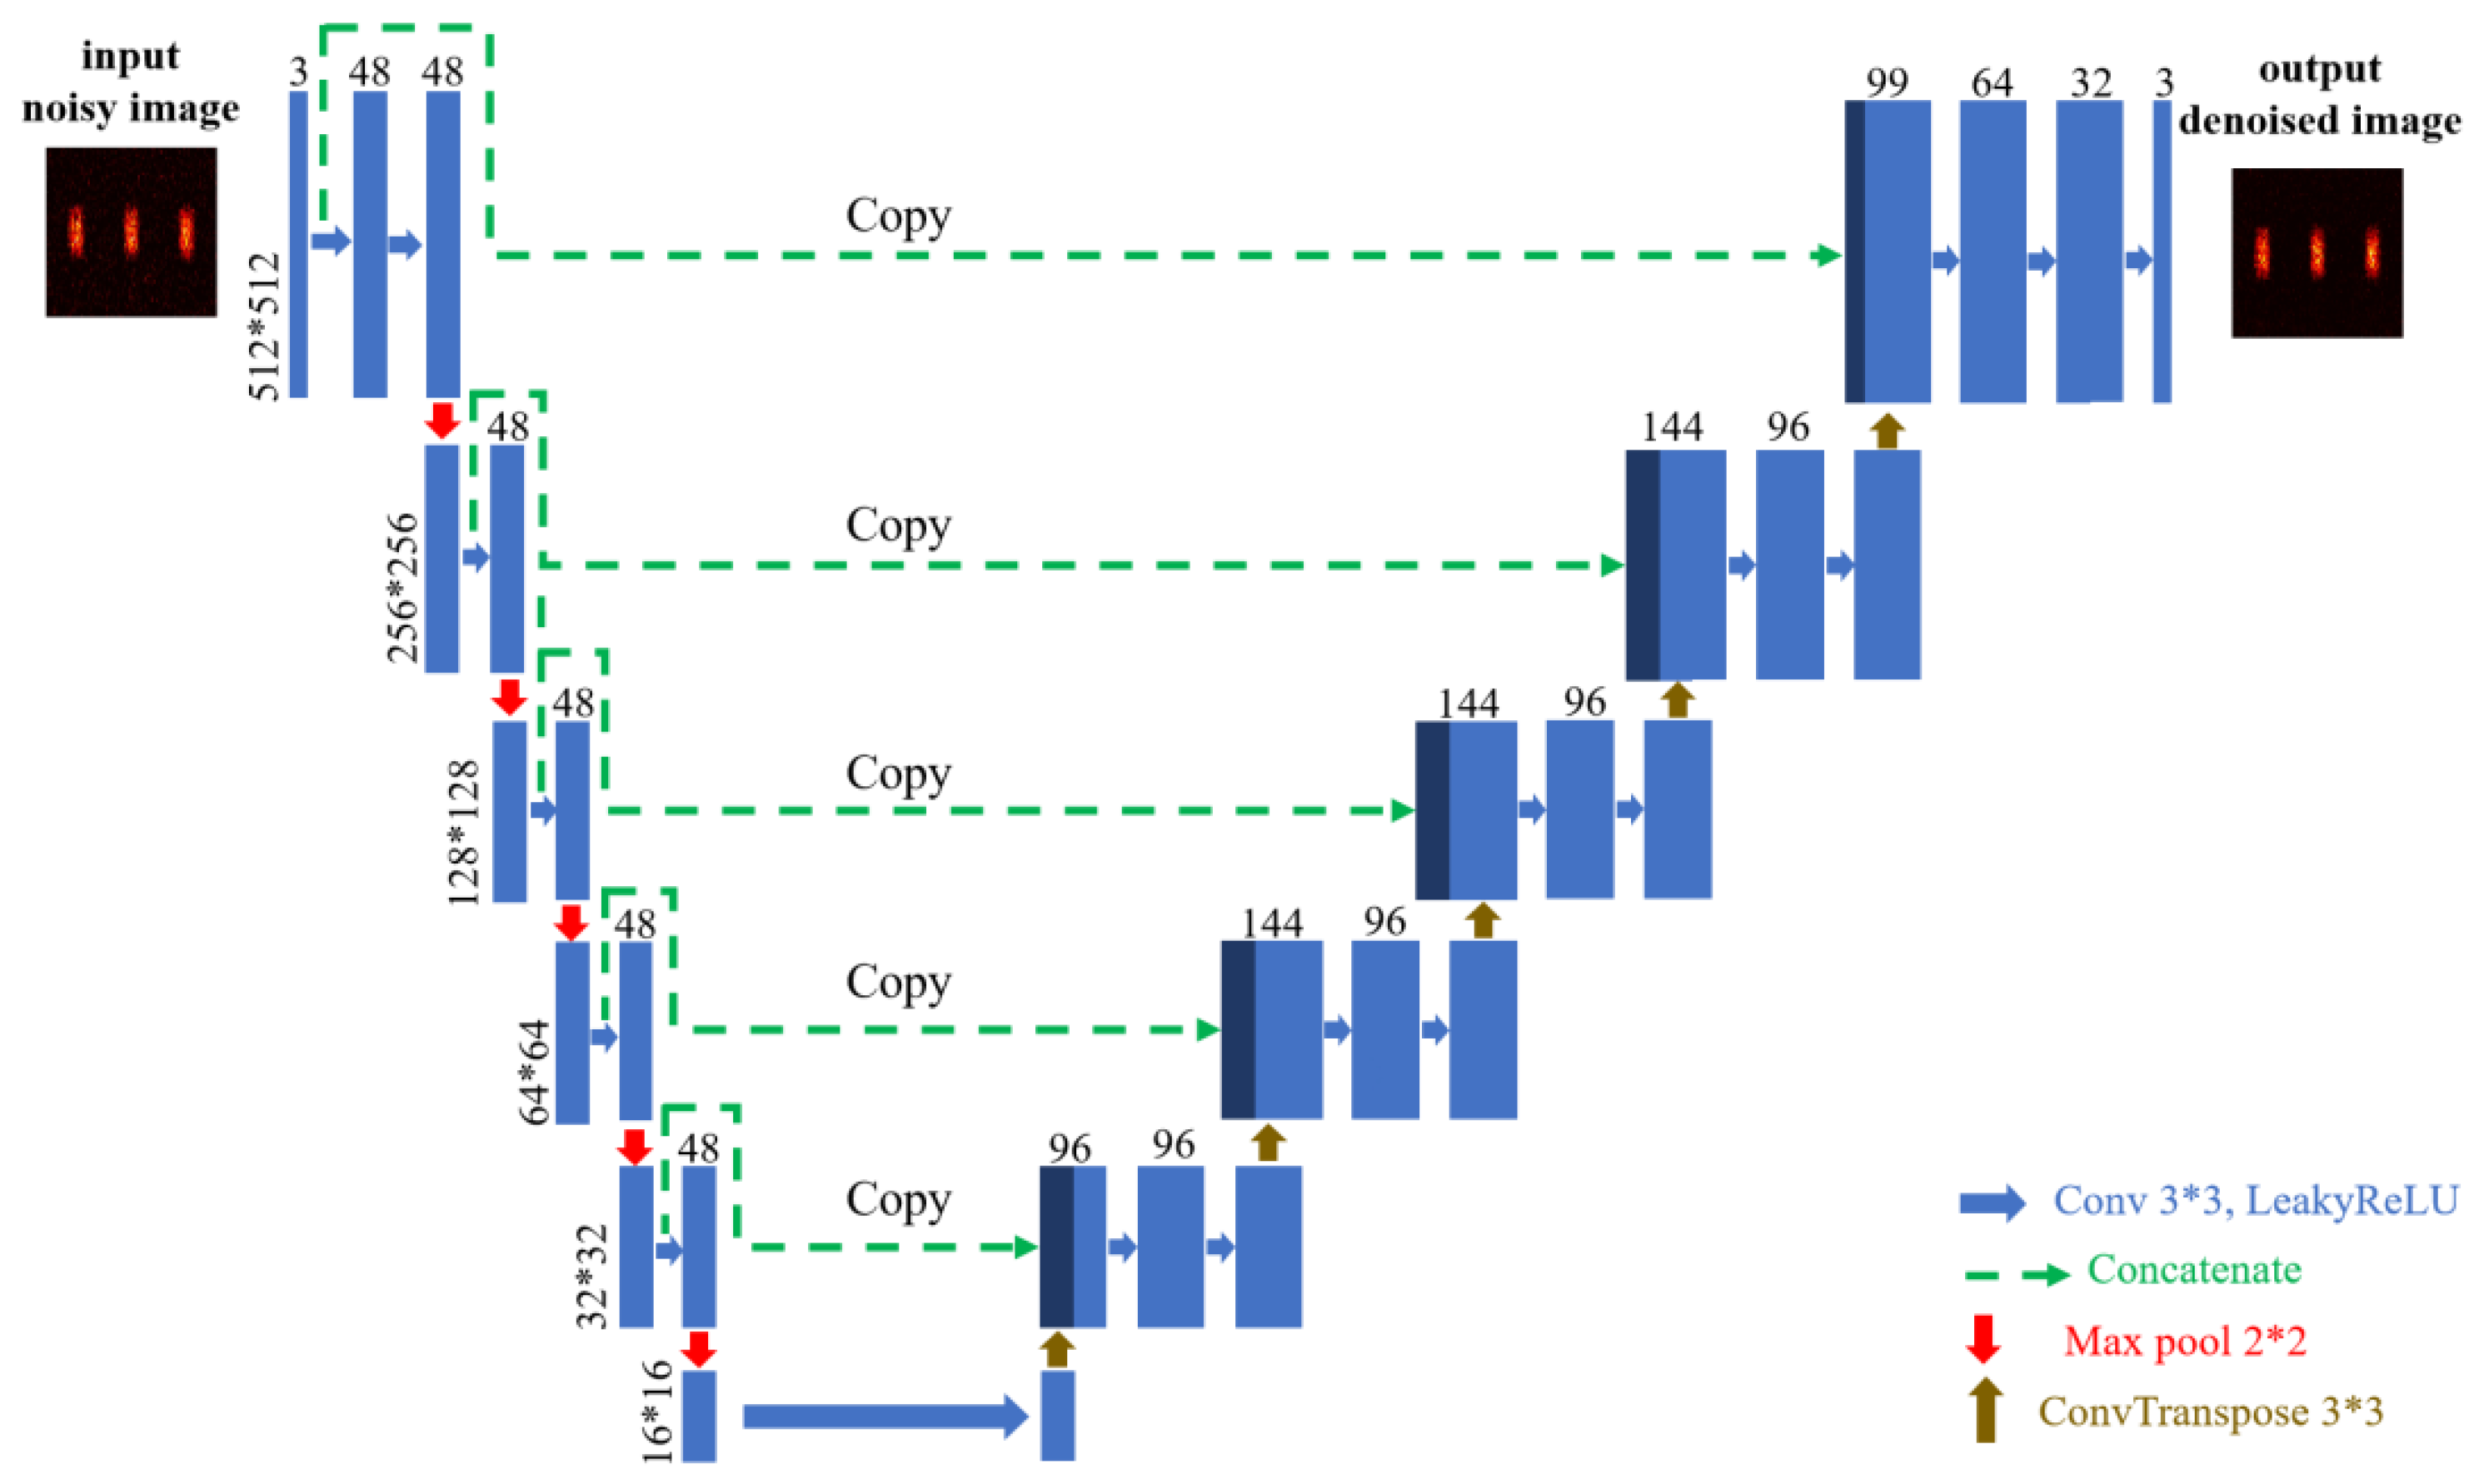

2.4. Network Architecture